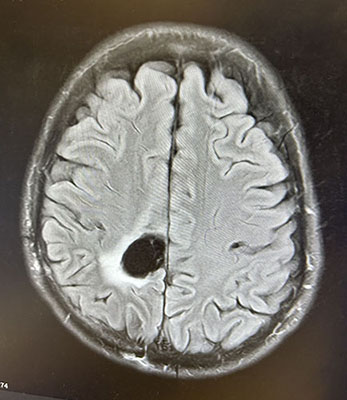

Cory’s brain scan.

At Mass General Brigham Cancer Institute, Cory met with neurosurgical oncologist Daniel Cahill, MD, PhD, and neuro-oncologist Nancy Wang, MD, MPH. As they explained, an MRI scan showed Cory had a glioma—the most common brain tumor in adults.

"At Mass General Brigham Cancer Institute we see hundreds of glioma patients every year," he said. "Cory's tumor looked different than the most commonly seen gliomas and had features suggesting it might be an oligodendroglioma. 'Oligos,' as we call them, are rare. About 1 in 15 patients who have signs of glioma on their MRI scan will have an oligo."